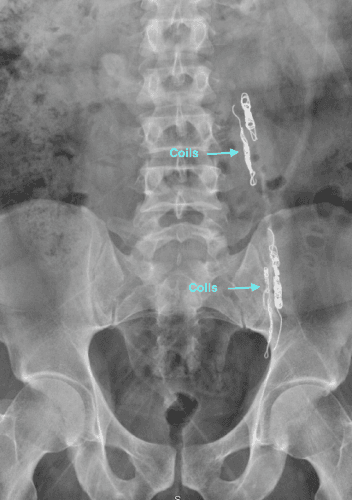

Varicocele can be treated by an embolization procedure or surgery. Embolization is a non-surgical, outpatient, minimally invasive technique that uses x-ray guidance to place tiny coils and embolic fluid in the abnormal blood vessels causing them to close down.

After a local anesthetic, a tiny catheter is placed into a vein in the groin or neck. The Interventional Radiologist then uses the x-ray equipment to guide the catheter into the variococele. A combination of metallic coils and a special fluid are placed directly into the abnormal veins causing them to close. Once the veins are blocked, the catheter is removed.